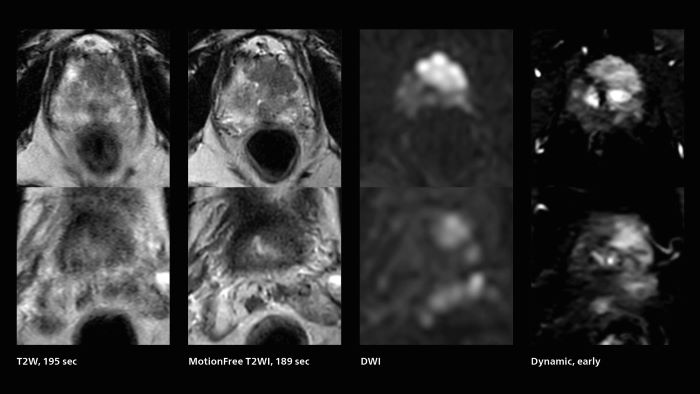

Prostate cancer MRI

MRI was performed in a patient with PSA 89.2. Evaluation of T2WI images was difficult due to rectal peristalsis. Using SmartSpeed MotionFree T2WI provided very good imaging quality. Seminal vesicle gland invasion is easily seen. Biopsy resulted in GS4+5=9. Performed on Elition X.

Prostate imaging with SmartSpeed

Given the high volume of prostate MRI performed at Kumamoto Chuo Hospital, the additional capabilities that SmartSpeed brings have a significant impact. “The clinical usefulness of SmartSpeed is clearly demonstrated in this area,” says Dr. Katahira. “Including SmartSpeed in most of our MRI protocols helps us improve the image quality.” The MRI team performs well over 20 prostate MRI exams per week. “In T2-weighted images we can get higher resolution,” says Dr. Katahira. “And while previously we were used to seeing blurred images due to rectal movements, introduction of the MotionFree SmartSpeed application allows us to obtain beautiful motion-compensated images, that are very useful for diagnosing, which was previously often impossible.” “In the diffusion-weighted images, we can use Compressed SENSE to obtain high quality images, and AI can be added to further improve image quality,” Dr. Katahira says.